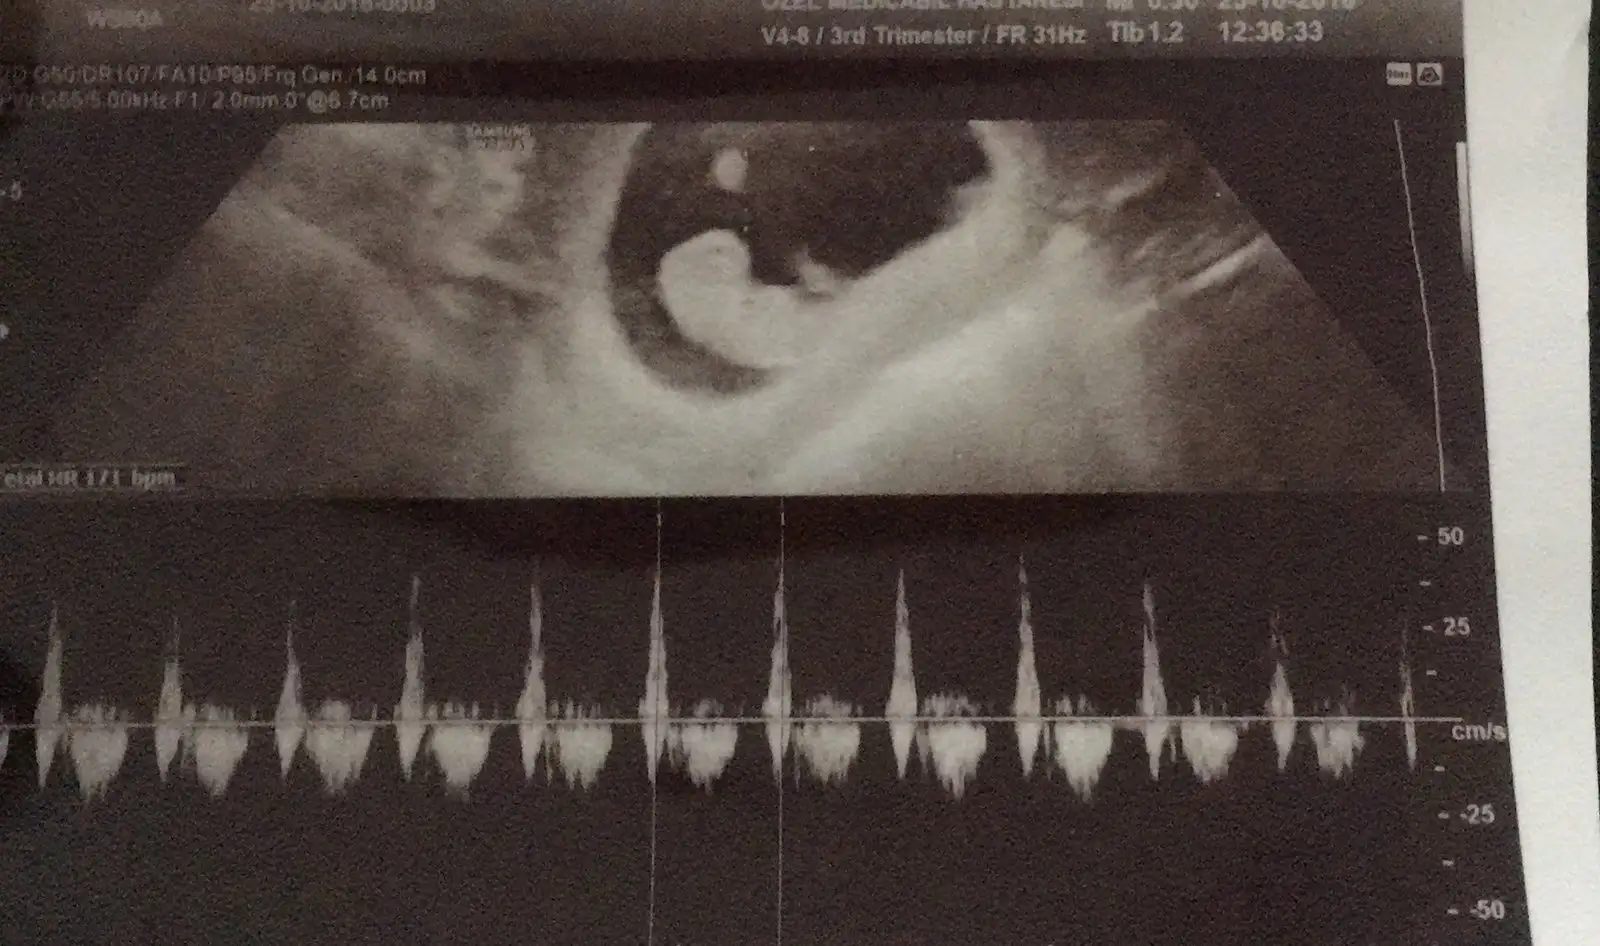

Paylaşırım tabi canım 9 haftalıktı bu görüntüde :)Usg görüntün varsa ilk haftaların paylaşır mısın bizimle

Heh bundan bahsedıyorum kızım sagdaydı senın solda :)))Paylaşırım tabi canım 9 haftalıktı bu görüntüde :)